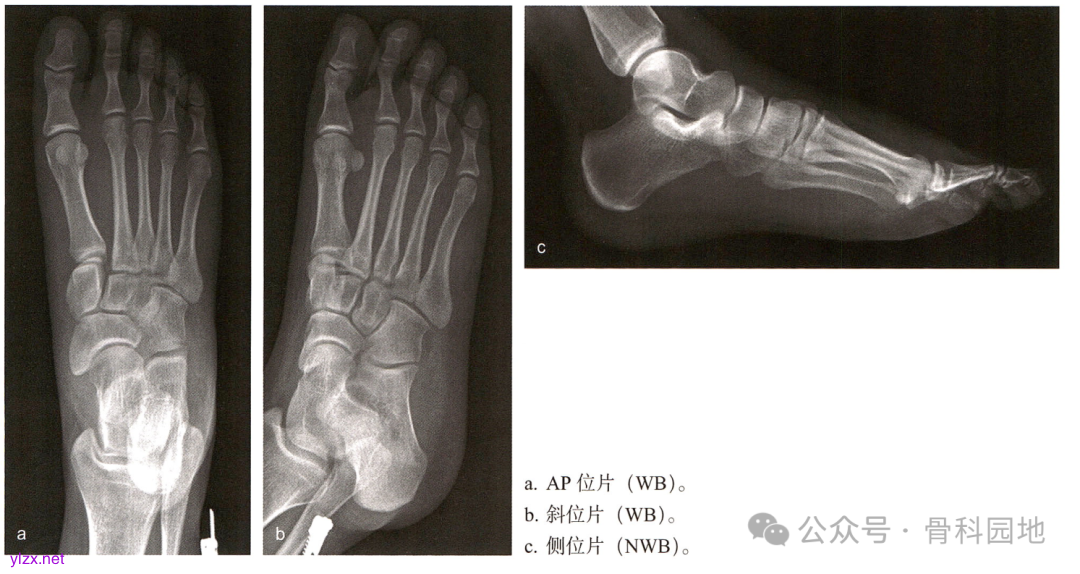

再现经典|跖附关节损伤(Lisfranc 损伤):经皮复位和固定的手术技巧和方法

如果 Lisfranc 损伤未经治疗,中足关节可能出现进行性畸形和继发性骨关节炎,从而导致预后不良。与非手术治疗相比,解剖复位内固定手术治疗疗效更好。对于轻微 Lisfranc 损伤,只要能够解剖复位,可以通过经皮技术完成。

病例: